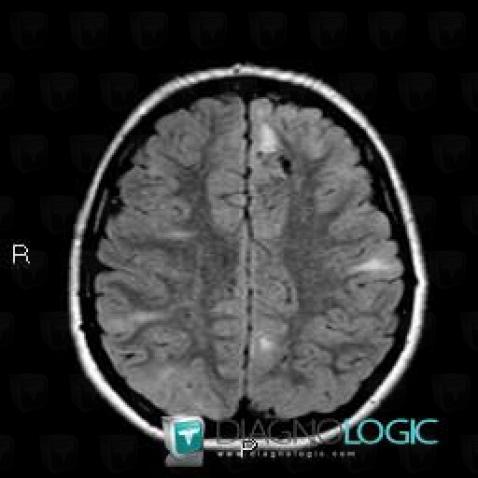

Here is the specific information in the key image above:

- Diagnosis Tuberous sclerosis (link to Hamartoma), Location(s) Cerebral hemispheres, with gamuts Multifocal intracranial lesions, Intracerebral T2W or FLAIR hyperintense lesion

- Diagnosis Hamartoma, Location(s) Cortico subcortical region, with gamuts Subcortical lesion, Cortical lesion

Here is the specific information in the key image above:

- Diagnosis Tuberous sclerosis, Location(s) Cerebral hemispheres, with gamuts Parietal posterior or occipital T2WI or FLAIR hyperintense lesion

- Diagnosis Tuberous sclerosis (link to Hamartoma), Location(s) Cortico subcortical region, with gamuts Cortical lesion, Subcortical lesion